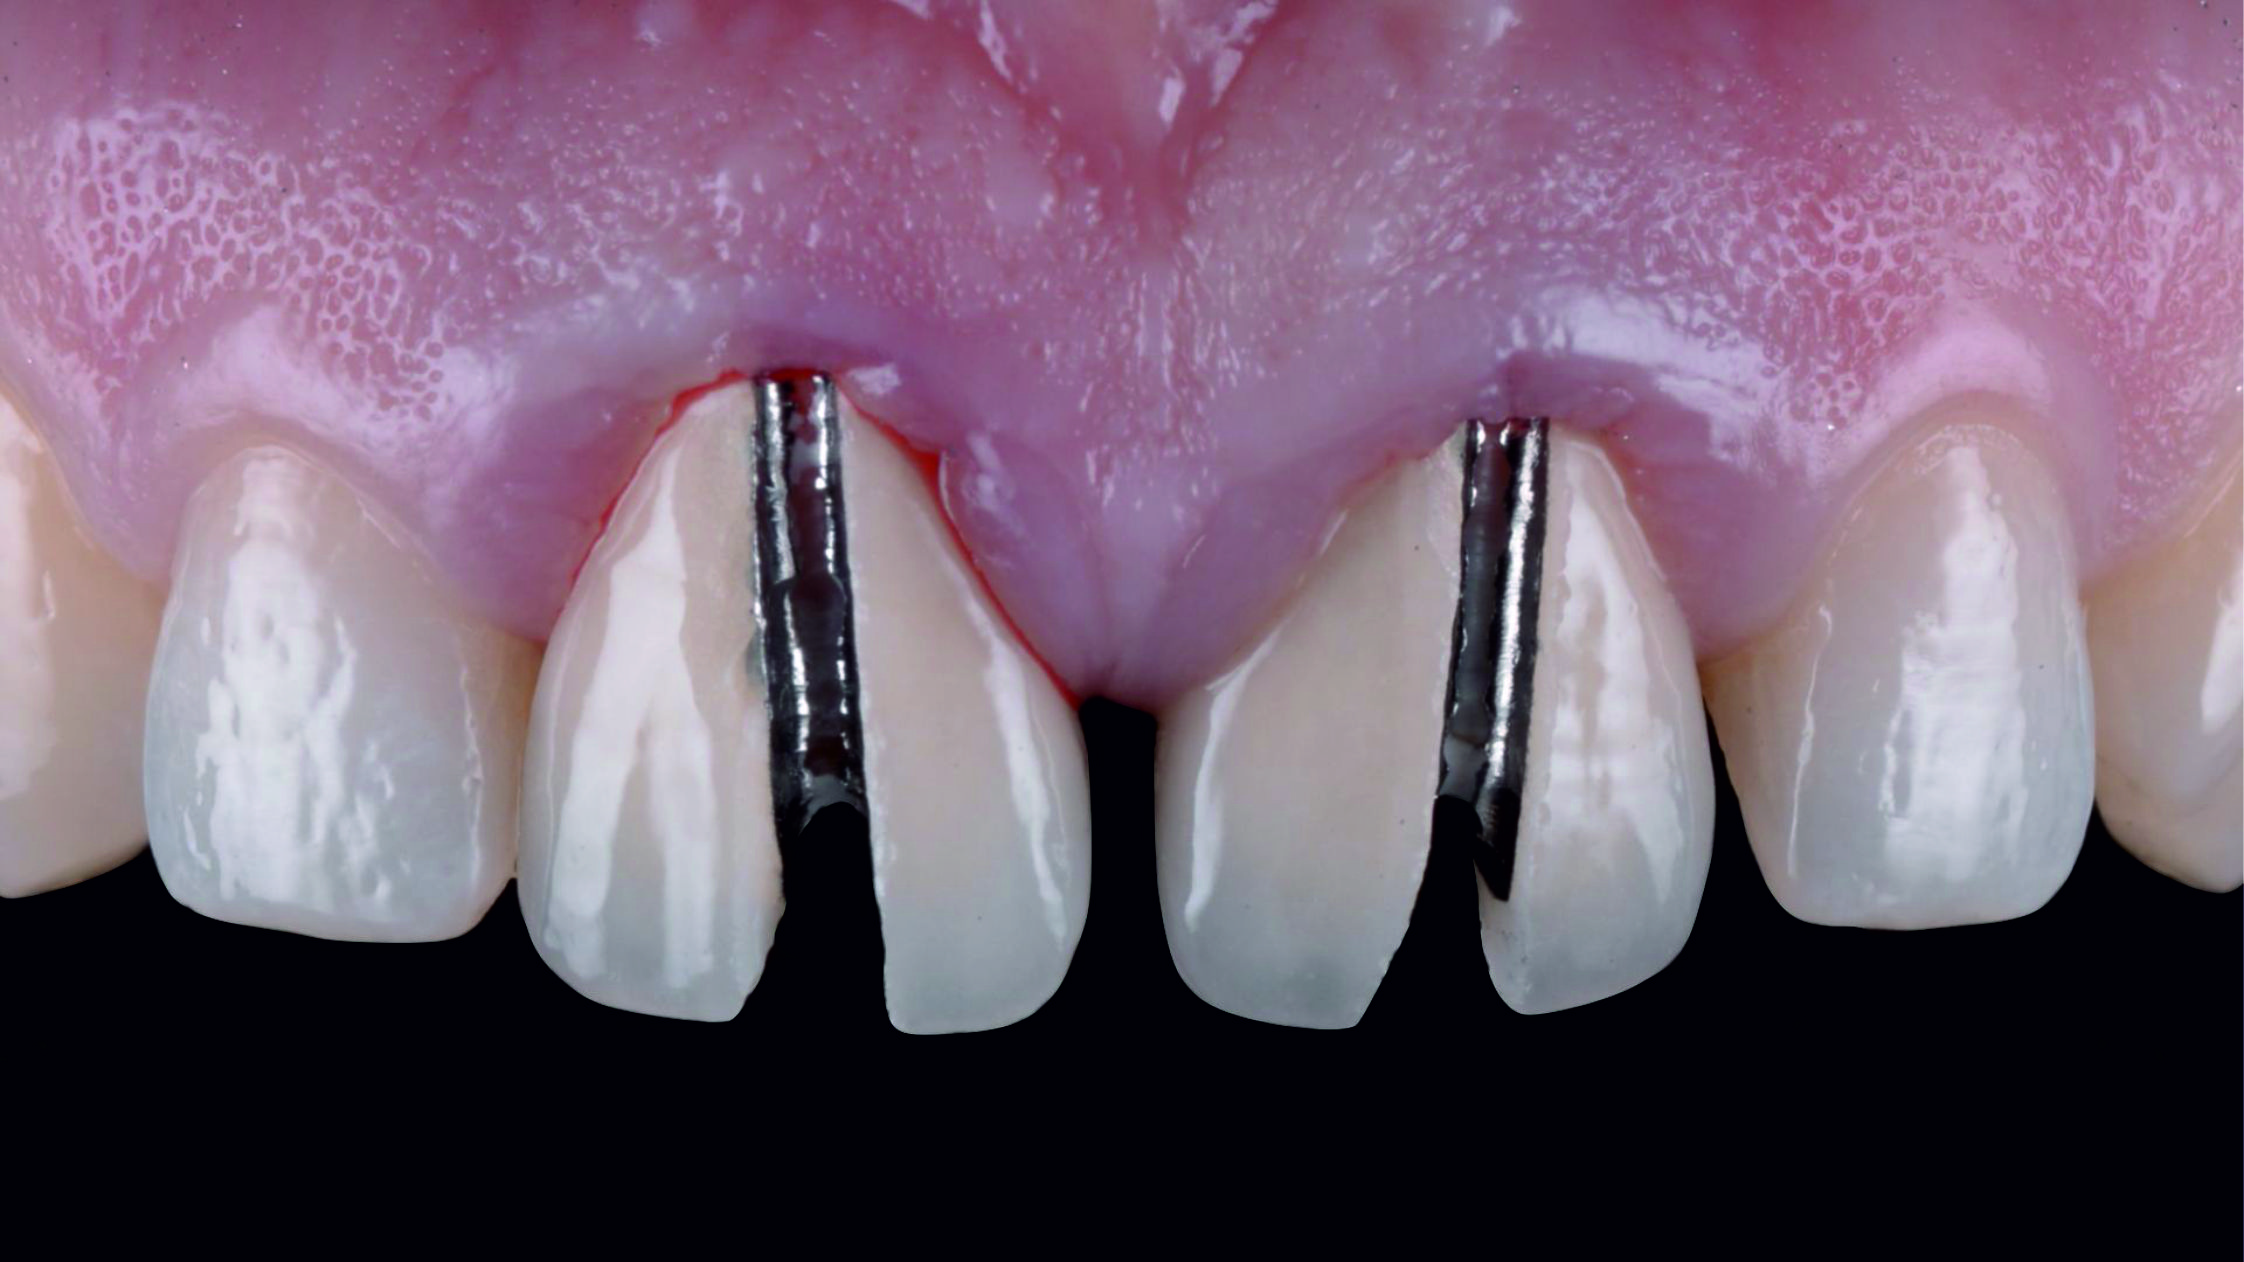

Фото 22. Щоб краще відкрити глибокі краї була використана техніка подвійної нитки. Це означає, що першу ретракційну нитку слід помістити в ясенну борозенку для вертикальної ретракції ясен і залишити там, а другу – частково занурити у борозенку для горизонтальної ретракції та видалити безпосередньо перед зняттям відбитка.

Фото 23. Тут видно, чим відрізняється ретракція ясен із використанням однієї нитки…

Фото 24. … від ретракції після видалення другої нитки.Фото 25. Існує безліч технік, які можна використовувати для передачі даних до лабораторії, але через низку причин найбільш надійною я вважаю одноетапну техніку, яка передбачає одночасне нанесення текучого матеріалу і маси-putty.